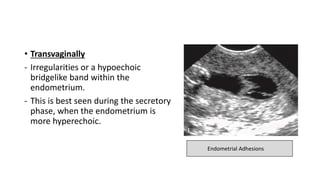

• Transvaginally

- Irregularities or a hypoechoic

bridgelike band within the

endometrium.

- This is best seen during the secretory

phase, when the endometrium is

more hyperechoic.

Endometrial Adhesions